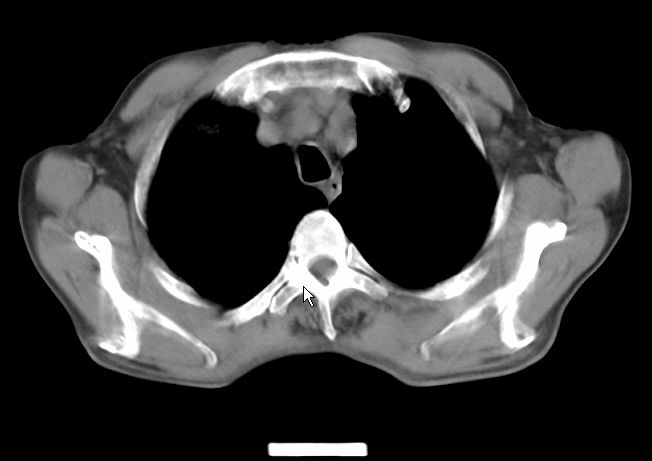

请大家看看是什么性质的。炎性病变首先考虑哪一种炎症。

炎性病变,金葡?建议痰检!

支持右肺上叶前段\\下叶内基底段感染,建议抗炎治疗后复查,除外结核.

楼主说是炎症,凭啥?典型的周围型肺癌(腺癌可能性大),肝内可能已有转移,强化看看吧。